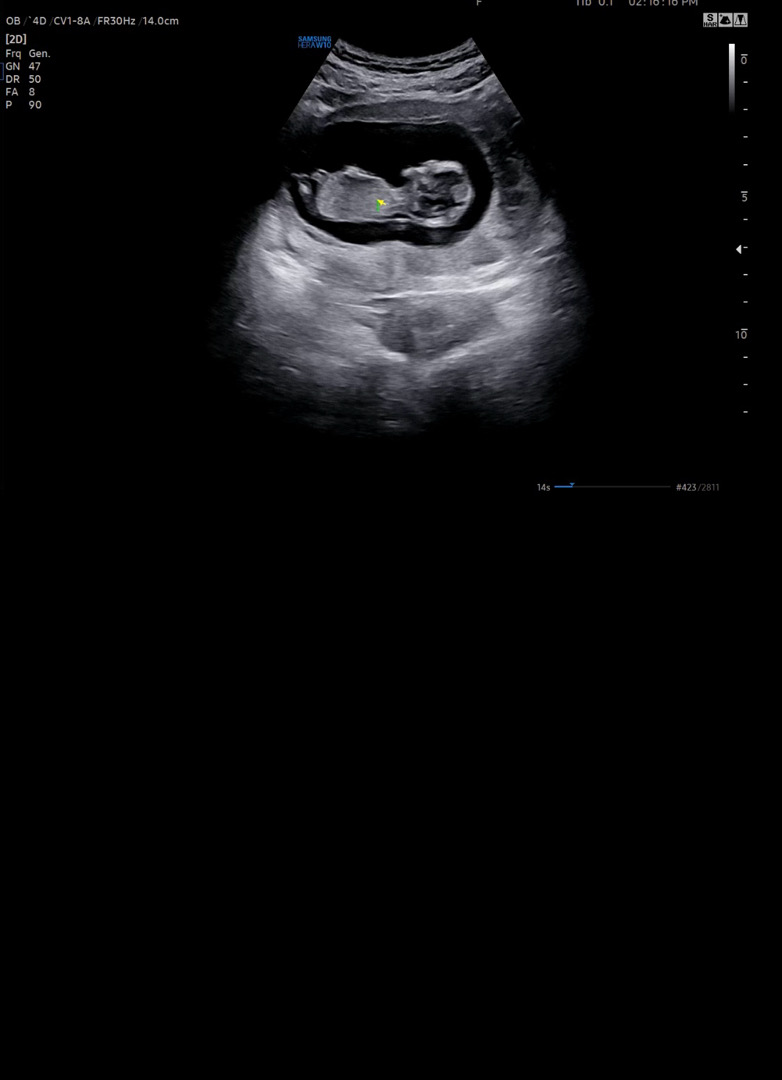

11주 6일 성별

방금 다녀왔는데 의사쌤이 뭐가 보인다고 조심스럽게 말해주셨거든요ㅠ 아들이겠죠...??딸을 원했는뎀

네 아들이네용